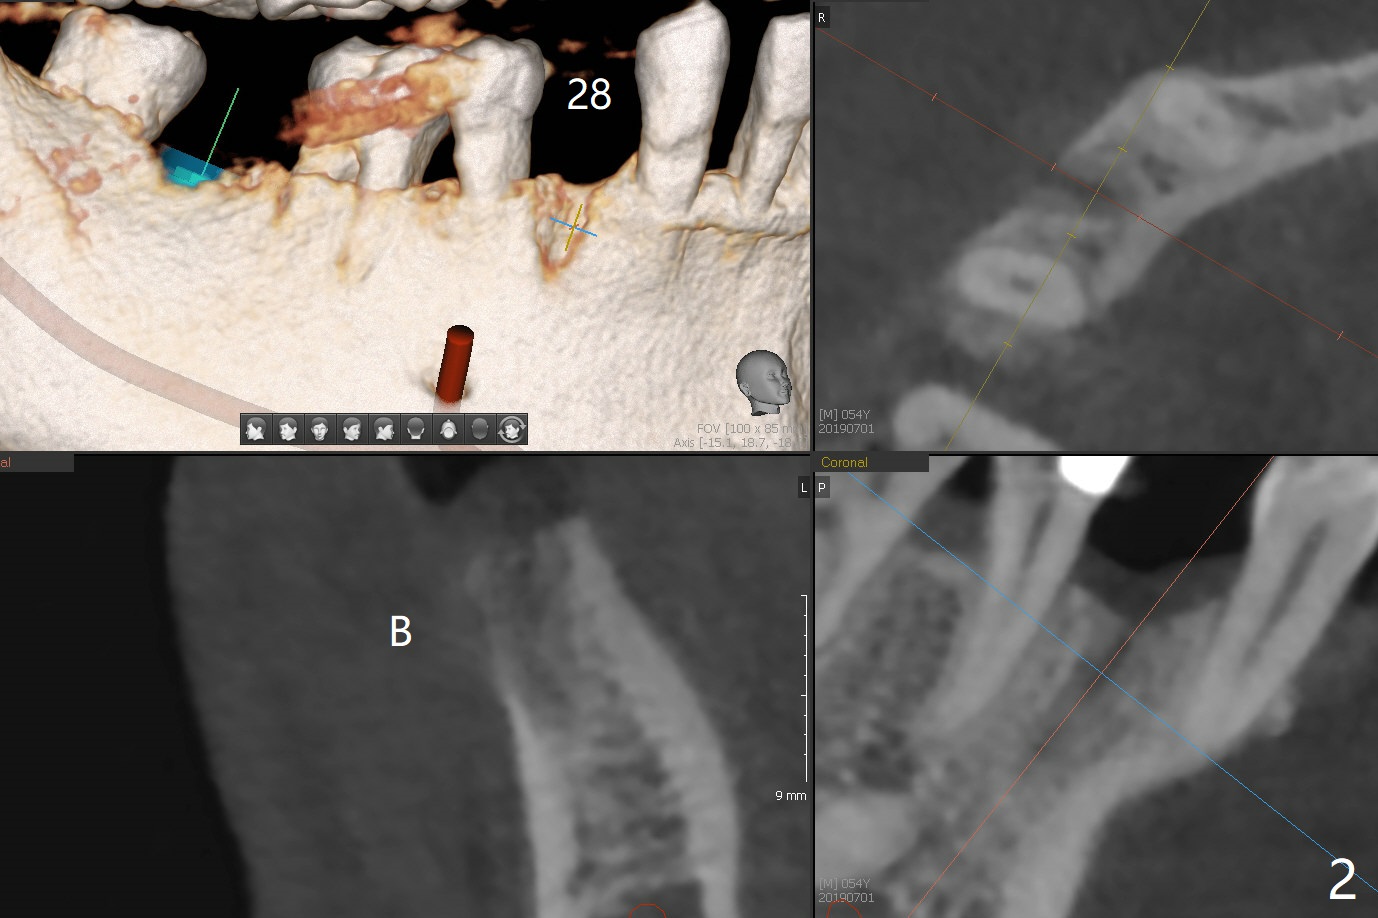

Bone Density Post Extraction with or without Bone Graft

Edentulous Lower Molar